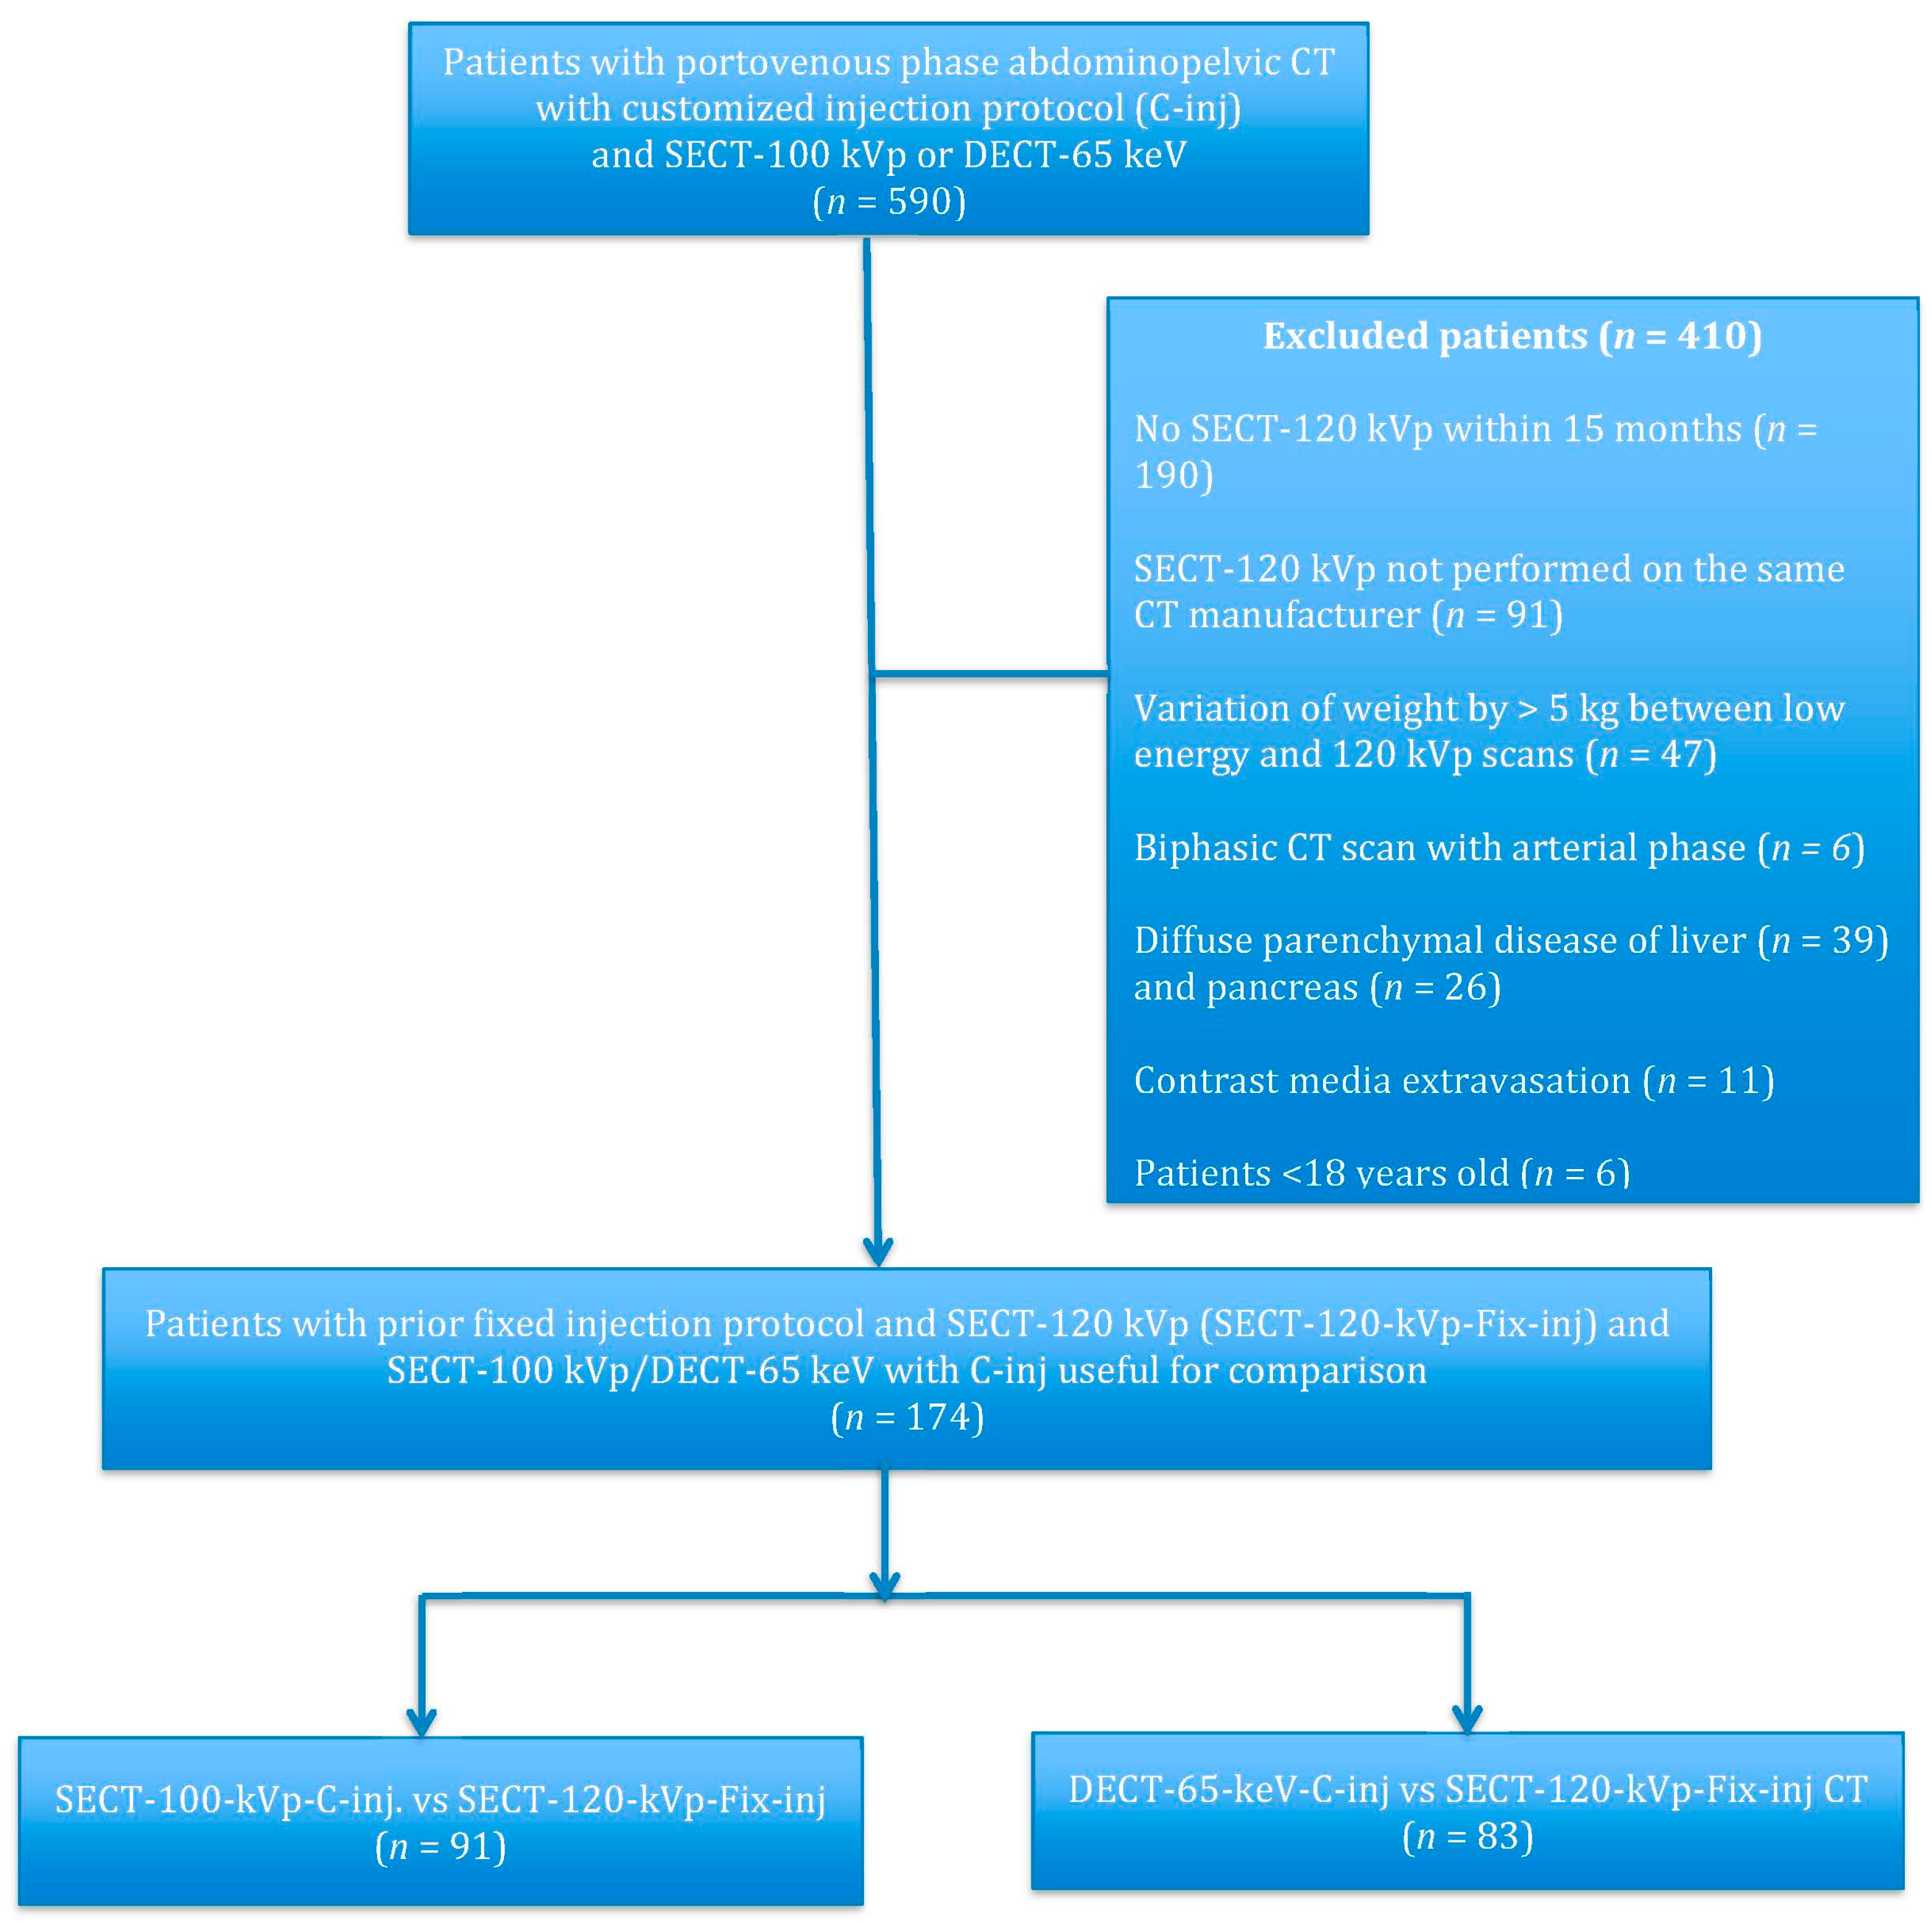

2.2. Patients

3.1. Patient Population